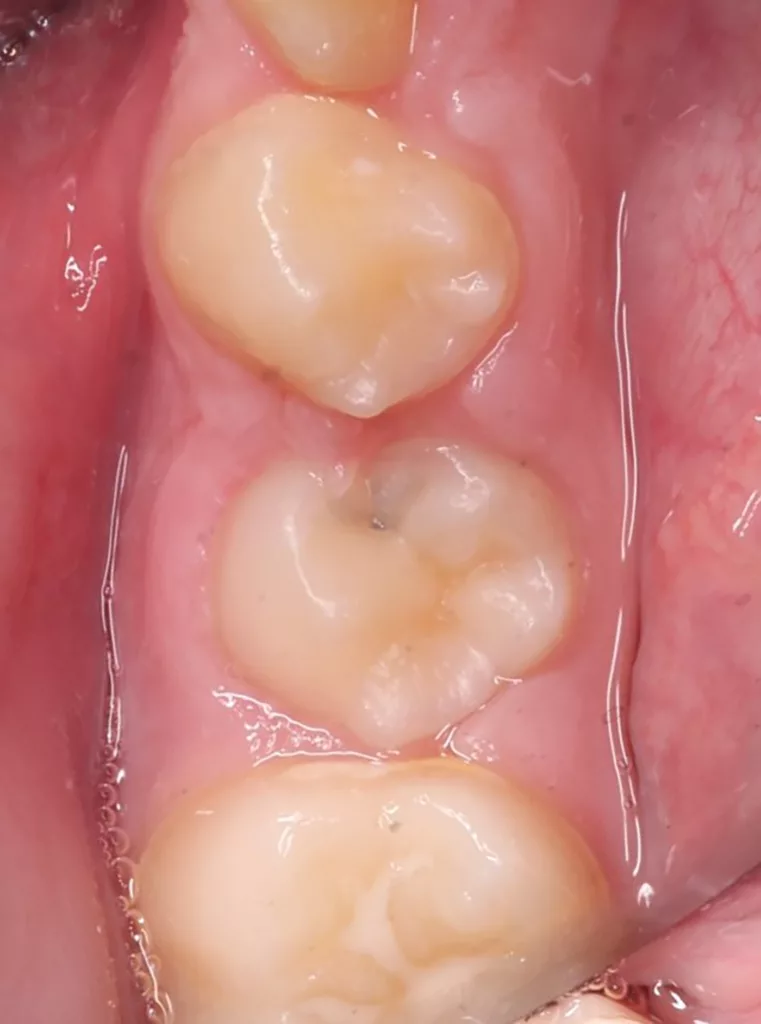

Im Rahmen der jährlichen Kontrolluntersuchung wurde bei einem achtjährigen Mädchen auf der routinemäßig angefertigten Röntgenaufnahme eine mittelgroße PEIR des Zahnes 46 (Grad 2 der Läsion nach Seow) entdeckt (Abb. 43). Die Patientin war komplett beschwerdefrei und der Zahnschmelz des betroffenen Zahnes sah intakt aus (Abb. 44 und 45). Weil auch hier der PEIR-Defekt gräulich durchschimmerte (Abb. 44 und 45) und der Zahn bereits seit einem Jahr durchgebrochen war, entschieden wir uns in diesem Fall, den Defekt klassisch mit Komposit zu restaurieren. Unter Lokalanästhesie mit Septanest 1/100 000 (Septodont, Frankreich) wurde zunächst Kofferdam mithilfe der Klammer U67 (KSK Dentech, Japan) gelegt (Abb. 45). Weder visuell noch mittels Sondierung konnte eine Verbindung zur Läsion festgestellt werden. Deswegen wurde an der Stelle, an welcher der PEIR-Defekt gräulich schimmerte, intakter Zahnschmelz der lingualen Querfissur entfernt (Abb. 46). Innerhalb der Läsion wurde nekrotisches intrakoronales Weichgewebe vorgefunden (Abb. 47), das problemlos mittels RONDOflex plus 360 (KaVo Dental, Deutschland) mit dem 27-µm-Pulver vollständig entfernt werden konnte. Der Boden des Defektes zeigte eine glatte, runde Form sowie helles, hartes und intaktes Dentin. Eine Präparation war nicht erforderlich, es wurde lediglich die Zahnschmelzkante geglättet (Abb. 48). Für die Restauration kamen erneut das Adhäsiv Optibond FL (Kerr, USA) und das Komposit Estelite ASTERIA OCE, A2B und Universal Flow AO2 (Tokuyama, Japan) zur Anwendung (Abb. 49). 6 Monate nach der Behandlung zeigte sich das Ergebnis sowohl aus klinischer als auch radiologischer Sicht stabil wie die Abbildungen 50 und 51 zeigen.